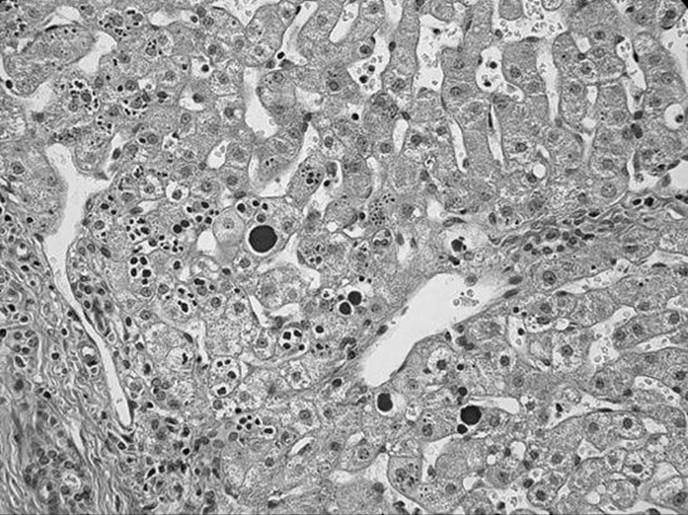

A 36-year-old woman presents with chronic hepatitis and is found to have an HLA B8 haplotype, liver/kidney microsomal antibodies, and elevated levels of serum IgG. Her liver biopsy is shown below. What is the most likely diagnosis?

Figure 51-5

Autoimmune hepatitis (type 2).

What is the most characteristic inflammatory cell seen in the infiltrate of a chronic autoimmune hepatitis?

Plasma cell.